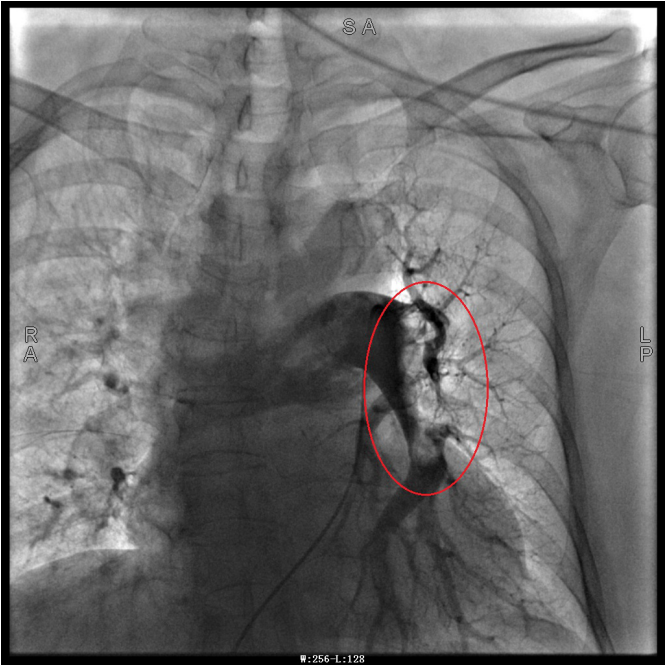

谭婆婆今年已经72岁了,因“突发意识障碍2次”到璧山区人民医院神经内科治疗。谭婆婆没有基础心脏病病史,但近段时间活动耐量明显下降,稍做活动就出现呼吸困难。入院后查BNP及心脏彩超均未提示明显异常,查D二聚体明显升高,经心血管内科周波医师会诊后转入科室继续治疗。在心血管内科主任、内科学(心血管病)博士于长青的指导下,周波医师成功完成医院首例“一站式”微创介入手术。在影像中,可以清晰地看到堵塞的血管经溶栓治疗后,重新畅通无阻,流动起支撑生命的血液。

肺动脉造影技术是目前诊断肺动脉栓塞的“金标准”,在全程心电监护下,通过股静脉或者颈内静脉置入鞘管后,利用导丝引导,将造影导管送入肺动脉;可在左/右肺动脉主干及其左右分支内,分别进行肺动脉造影或选择性肺动脉造影,存在栓塞的肺动脉血管在造影剂注入后即会显示出充盈缺损、充盈缓慢、或者血管显影模糊,严重栓塞的肺动脉血管甚至会出现血流截断征象。

肺动脉导管局部置管溶栓术是通过肺动脉造影确定堵塞的肺动脉部位,然后导管尖端置于血栓处,将尿激酶、链激酶或重组组织型纤维蛋白溶酶原激活剂直接注入血栓处,新鲜血栓在足量的溶栓剂作用下溶解。肺动脉内局部用药特别是小剂量时可减少出血并发症。

注明:第一张、第二张为术前图像